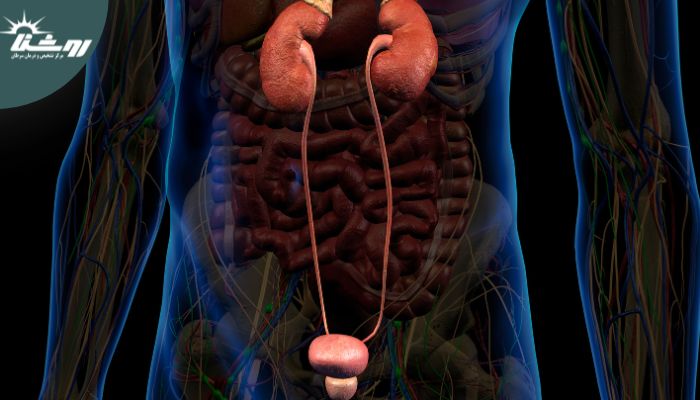

کیستهای کلیه حفرههای پر از مایعی هستند که بر روی یا درون کلیهها تشکیل میشوند. این کیستها میتوانند در اندازهها و تعداد متفاوتی باشند و اغلب بدون آسیبزدن به عملکرد کلیهها وجود دارند. با این حال، در برخی موارد، کیستها میتوانند باعث علائمی شوند که نیاز به توجه پزشکی دارند. کیستهای کلیه معمولاً خوش خیم هستند اما باید دقیقاً تحت نظر گرفته شوند تا اطمینان حاصل شود که آسیبی به کلیهها وارد نمیکنند.

برای تشخیص کیستهای کلیه، پزشکان معمولاً از روشهای تصویربرداری نظیر سونوگرافی، سیتی اسکن، یا MRI استفاده میکنند. این روشها به تعیین محل دقیق، اندازه، و ساختار کیستها کمک میکنند و در تصمیمگیری برای نیاز به درمان یا نظارت بیشتر مؤثر هستند. مرکز تصویربرداری روشنا بهترین مرکز سونوگرافی در غرب تهران شناخته شده است که خدمات تصویربرداری دقیق با استفاده از دستگاههای پیشرفته و تیمی از متخصصان با تجربه ارائه میدهد. استفاده از این مرکز برای اطمینان از دقت تشخیص و کیفیت بالای خدمات توصیه میشود.